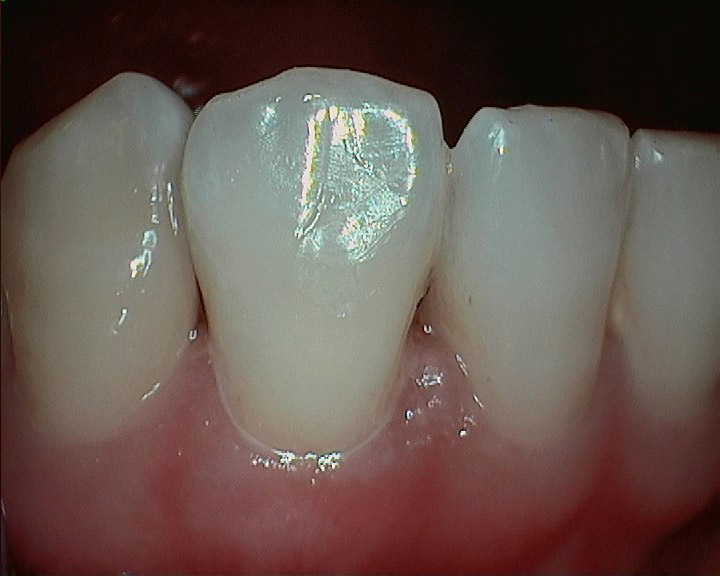

Trauma Case.

The patient had an accident and broke her lower front tooth. We put the fragment back and it looks just as nothing happened.

Tooth Fragment.

For a regular dentist, this may take 2 -3 appointments to fix, more tooth structure loss due to crowning, and might cost thousands of dollars. However, with Dr. Tao's expertise, such problems can be easily fixed with accuracy and high-quality in as little as one day.